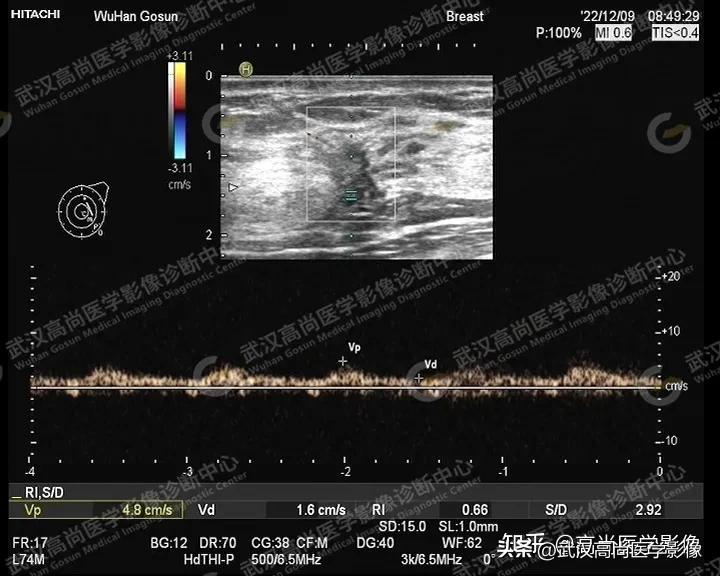

图四:肿块内血流信号丰富,RI:0.68。